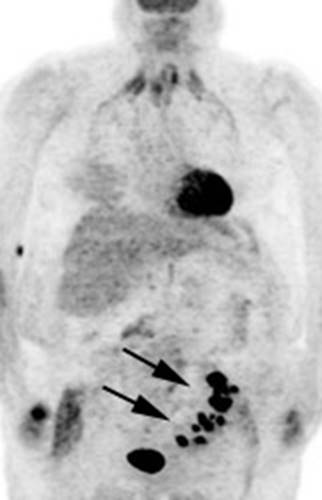

Figure 6 - Genitourinary activity: The image below

demonstrates activity within the collecting system of a transplanted kidney

(black arrows). This should not be mistaken for an abnormality.

Figure 7 - Bladder cancer: Despite urinary excretion

of the radiotracer, this patients bladder cancer

(white arrows) is readily identified on the PET scan (black arrows). In

general, however, urinary excretion of FDG limits evaluation of urinary tract

malignancy